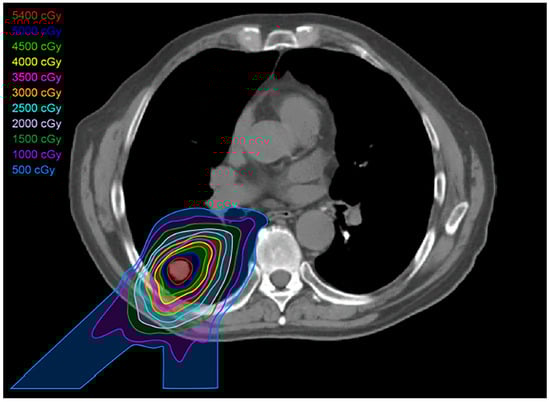

2.2. Three-Dimensional Conformal Radiotherapy

2.3. Intensity-Modulated Radiotherapy

2.4. Stereotactic Body Radiotherapy

2.5. Four-Dimensional Conformal Radiotherapy

2.6. Proton Therapy